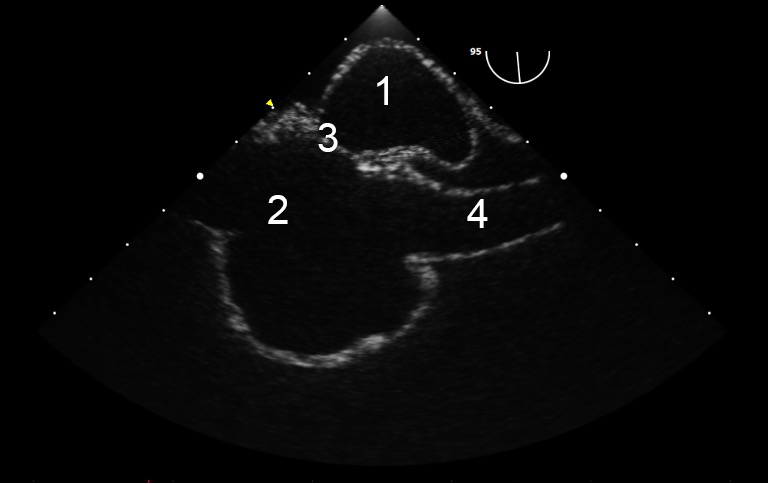

TEE Resus Mid-esophageal Bicaval IU 2 Image

Left Atrium

Right Atrium

IAS

Super Vena Cava (SVC)